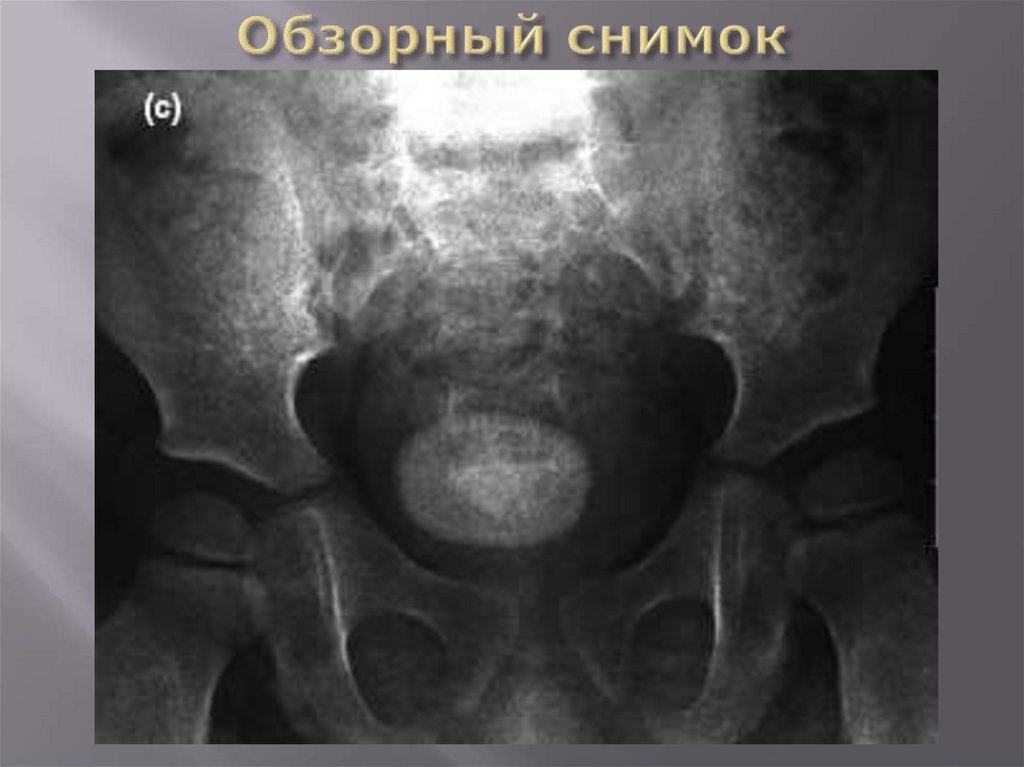

Обзорный снимок